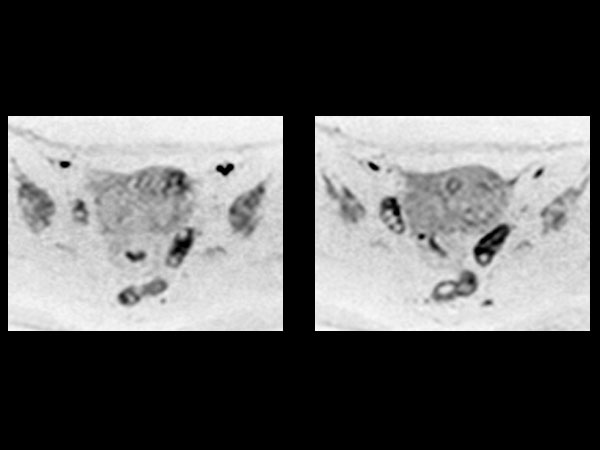

Female Pelvis

Toyonaka Hospital, Japan